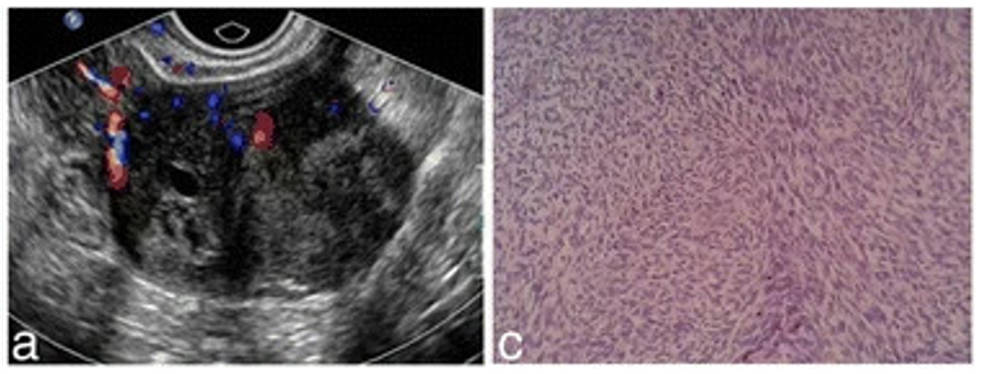

Fig 1. Ultrasound and pathological features of an ovarian cellular fibroma.Fig 1. Ultrasound examination and pathological findings

proved to be cellular fibroma.1

Pathological Features: Ovarian fibromas typically have a round, oval, kidney-shaped, or lobulated appearance, with a smooth surface and firm, hard texture. They are encapsulated tumors composed mainly of fibroblasts arranged in bundles or interlacing patterns, with these cells being spindle-shaped or oval in morphology.

1. Chen, H.; et al. Ovarian thecoma-fibroma groups: clinical and sonographic features with pathological comparison. J Ovarian Res. 2016, 9(1): 81. Distributed under Open Access License CC BY 4.0. The original image was modified by keeping part (a) & (c).